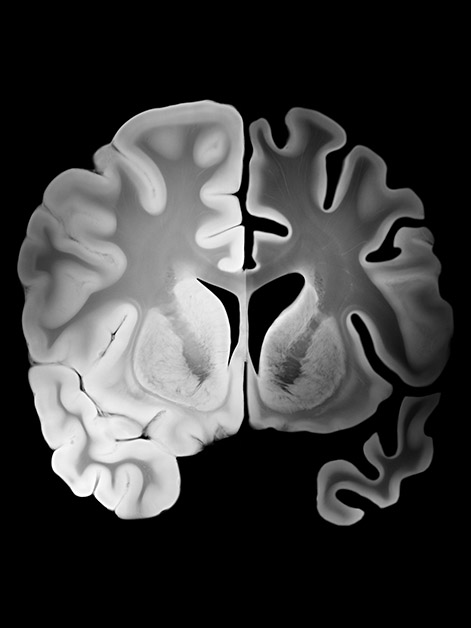

As the world’s population ages, neurodegenerative diseases – including Alzheimer’s – are becoming an increasingly serious public-health challenge. The effectiveness of existing treatments, including those approved in recent years, has yet to be firmly established, and there is an urgent need for new therapeutic approaches. One of the central hallmarks of Alzheimer’s disease is the accumulation of amyloid-beta protein plaques in the brain, accompanied by signs of inflammation in brain tissue.

The research team headed by Prof. Ido Amit of Weizmann’s Systems Immunology Department and Prof. Jonathan Kipnis of WashU Medicine, and led by WashU Medicine postdoctoral fellow Dr. Pavle Boskovic, isolated T cells from the immune system of healthy mice and genetically engineered them to recognize and respond to amyloid proteins in the brain. The researchers then injected these engineered cells into mice whose brains already contained amyloid-beta plaques characteristic of Alzheimer’s disease. The injections led to a significant reduction in amyloid deposits, as well as a decrease in markers of brain-tissue inflammation.